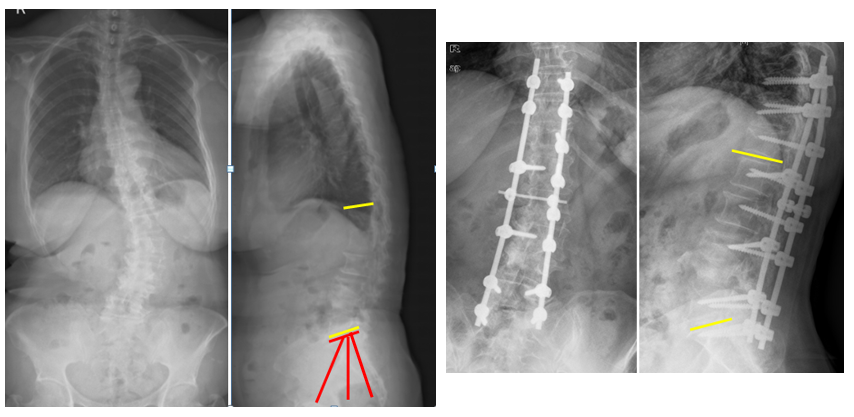

T10骨盆固定,出现交界性后凸

行翻修手术:T9/10SP截骨,延长到T4固定,预防性双侧肋骨固定(VEPTR)

图32-33 肋骨固定